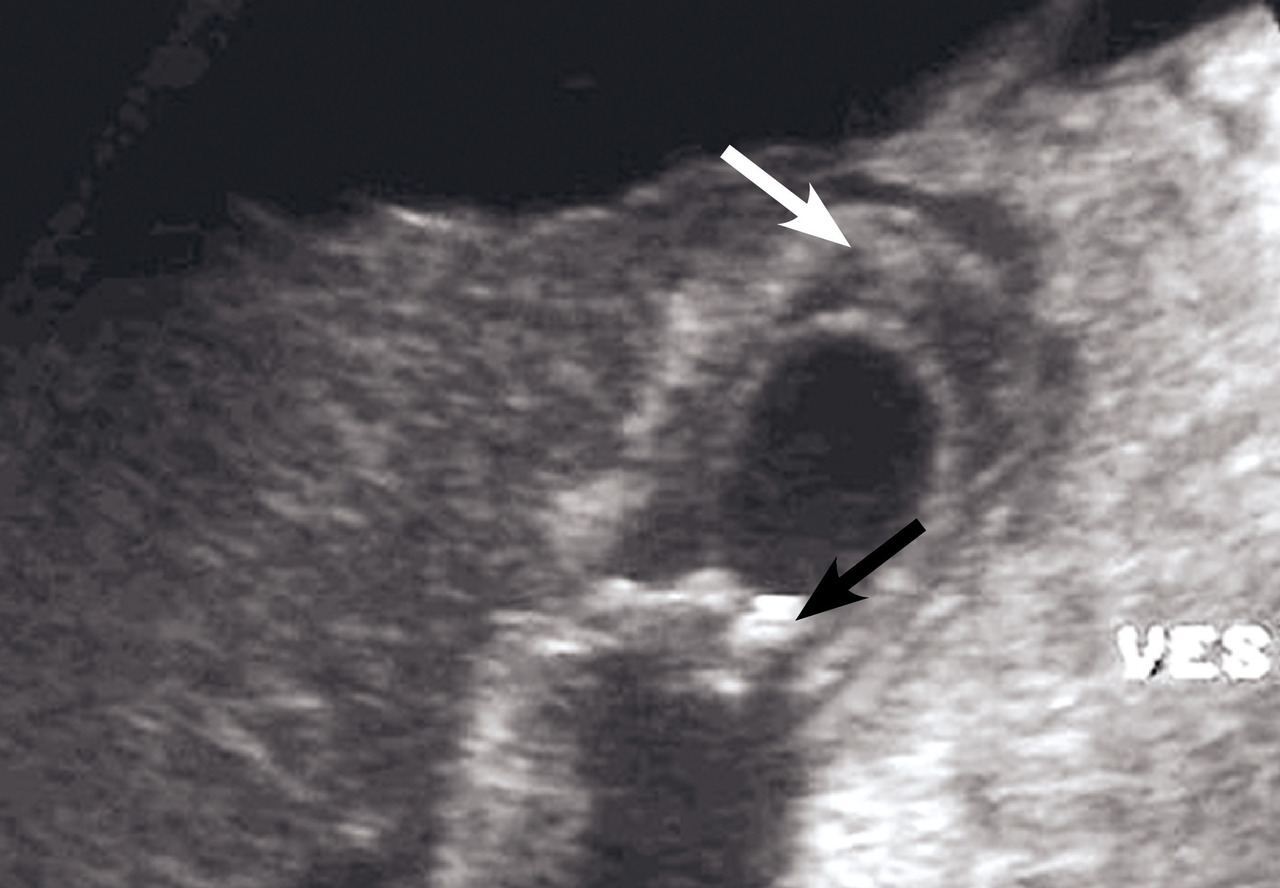

L’échographie abdominale a l’inconvénient d’être opérateur-­dépendante. Ses principales indications sont la lithiase biliaire et ses complications, des douleurs abdominales chez les patients minces et surtout chez la femme pour rechercher une pathologie gynécologique en utilisant le cas échéant des sondes endocavitaires. Ainsi, l’échographie est utile pour affirmer la lithiase biliaire et la cholécystite aiguë (fig. 1) ou objectiver une dilatation de la voie biliaire principale (VBP), rechercher une urétéro-hydronéphrose et des signes indirects en cas de colique néphrétique (fig. 2 et 3), débrouiller le diagnostic des douleurs abdomino-­pelviennes chez la femme.

L’échographie est essentielle, montrant un épaississement de la paroi vésiculaire à plus de 6 mm et la présence de calcul(s) ou « sludge » (fig. 1), sans dilatation de la voie biliaire principale (VBP). La complication principale est la péritonite et le choc septique souvent sur une gangrène de la paroi vésiculaire qui peut conduire de manière exceptionnelle vers le cholépéritoine.

L’échographie peut montrer une discrète asymétrie des cavités excrétrices rénales, voire l’obstacle lithiasique avec dilatation d’amont (fig. 2 et 3). L’uroscanner complète le bilan et localise si besoin le calcul. Outre le traitement de la cause (calcul, compression extrinsèque…), le traitement antalgique est primordial : anti-inflammatoires non stéroïdiens (AINS), paracétamol, anti­spasmodiques voire dérivés morphiniques. On procédera à la pose d’une sonde urétérale en cas d’anurie (rein unique), de fièvre sur rétention du haut appareil ou de crise hyperalgique.